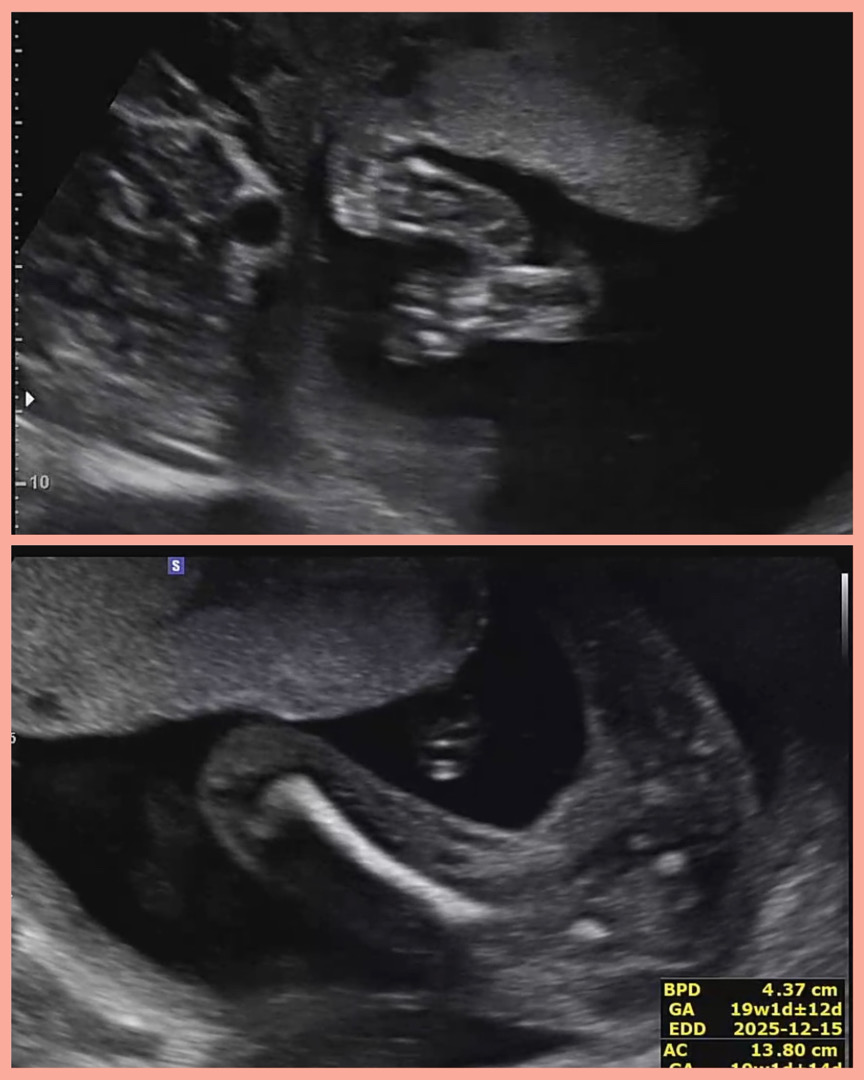

👣🌸 19주에 찍은 발바닥이랑 똘램 존재감 확실(?)한 스크린샷입니다 오늘 자다가 오른쪽 배가 전에 없던 찢어지는 느낌으로 찌르는듯이 아파서 놀라서 병원갔더니 애기가 배꼽쪽으로 올라올만큼 커져서 자궁주변 인대가 늘어나서 간헐적 통증을 느낄 수 있다고 하시더라구요 .. 주기적으로 잦게 반복되거나, 지속적인 통증이면 당장 병원오고 그런거 아니면 보통은 자연스러운 일이라고 알려주셨어요 온김에 애기 잘 있는지 보자고 하시면서 사진도 여러장 찍어주셨답니다 ㅎㅎ 2주뒤에 정밀초음파 보러가는데 떨리네요🙏🏻 그래도 오늘 활발한 아기 보니 반갑더라구요 엄마들 더운데 모두 힘내셔요